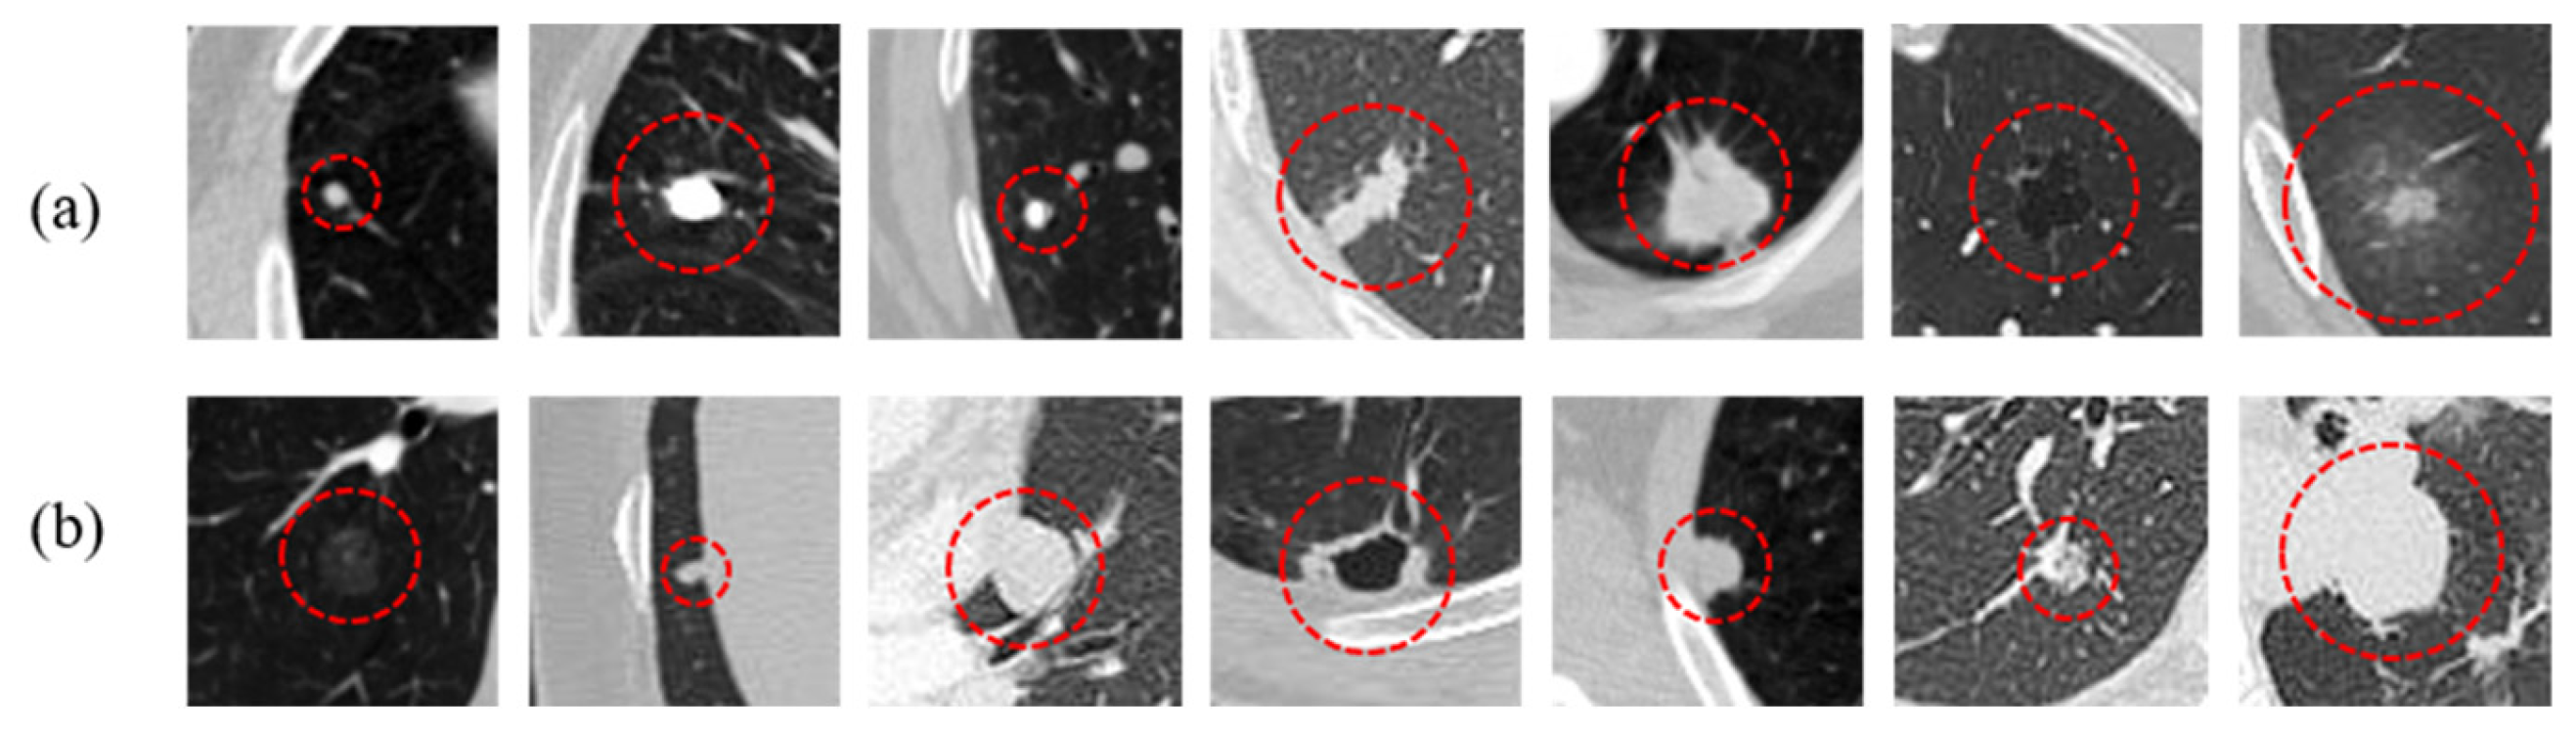

5.3. Qualitative Analysis